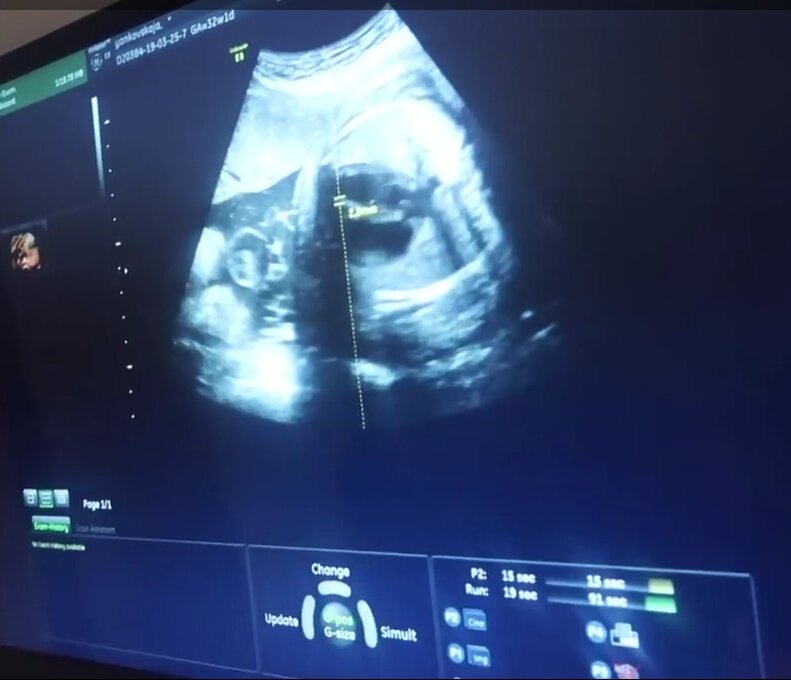

Каждая Беременная должна знать об этих болях. Или как уберечь своего ребёнка и себя.